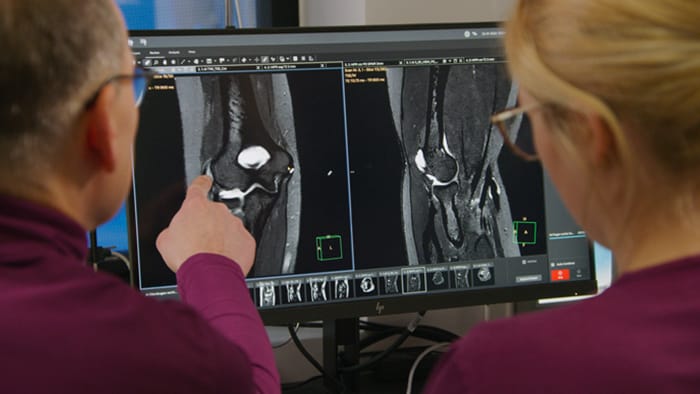

After acquiring Philips SmartSpeed, Dr. Tobias Schröter was astonished at the great potential of this technology. It sets the stage for rapid, high quality MRI exams in his practice. He points out that across all anatomies, he discovers that shorter scan times and exceptional detail means faster, more confident diagnoses. Patient throughput has improved by about 20 percent.

Dr. Tobias Schröter, MD, has been a radiologist since 2000. After running a 24/7 radiology practice for 16 years, he took over MRT-Praxis Potsdam, specializing in MRI diagnostics. “After the takeover, I completely redesigned the premises and exchanged the older MRI machine for a 1.5T Philips Ingenia Ambition S with sealed magnet.” Recently, the MRI Practice in Potsdam acquired AI-based Philips SmartSpeed of which Dr. Schröter has found that it makes a significant difference. “We had already been using Compressed SENSE from Philips to accelerate our cartesian scans and increase throughput. SmartSpeed now allows us to further reduce scan times and artificial intelligence (AI) makes the image quality even better compared to images we acquired using Compressed SENSE.” Dr. Schröter now uses SmartSpeed for 2D and 3D sequences in all anatomies. “I am astonished at the great potential of SmartSpeed, especially because 3D imaging in MSK is becoming feasible now. I can get very good image quality in very short scan time.” He also uses SmartSpeed for patients that cannot hold still, without worrying about needing re-scans. And it can also be used for patients with implants. “Besides the fast scanning, we now have the advantage of fast image reconstruction, so that we can already look at images while the scanning is still ongoing.”

“The big 27-inch 4K high resolution screen makes a total difference. It shows the large planning images with much higher resolution than we were used to. Anatomic landmarks can be more easily identified, which advances the process. Now it is much easier and faster to plan the new sequences and it’s easier for us to find lesions,” says Dr. Schröter.